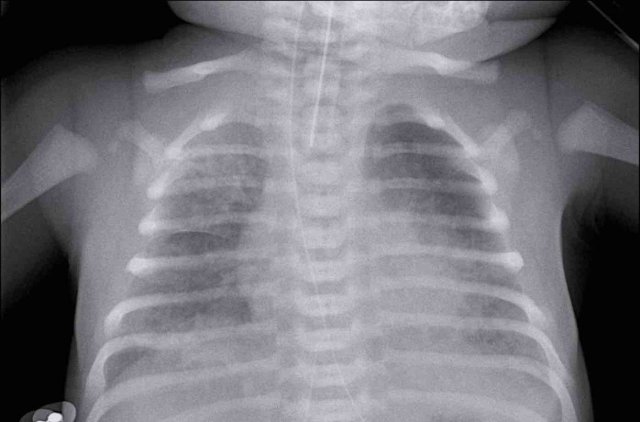

Premature of 25 weeks and 5 days, now 2 month old. Treatement for RDS

1. The first chest radiograph shows hyperinflation, and a markedly enlarged heart with increased vascular markings and interstitial markings.

NG tube and duodenal tube in situ.

2. After 5 days of treatment there is less hyperinflation and normalization of the heart size and vascular markings.

There still remain some interstitial markings, in keeping with BPD.